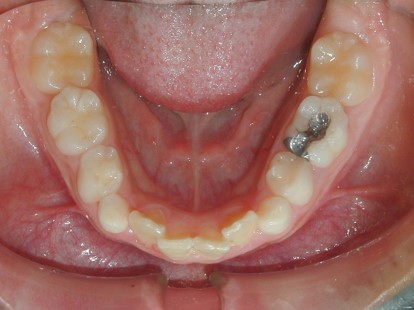

永久歯に交換するためのスペース不足による前歯のガタガタで、取り外しができる拡大床にて上下顎の幅を拡大した後、上顎の前歯をマルチブラケット装置で並べました。治療の期間は1年9か月でした。

初診時

終了時